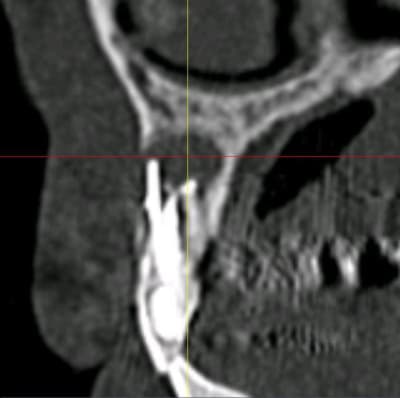

bon, c'est le cas clinique d'un pote (sera peut être plus ensuite, qui sais...) qui c'est décidé de venir me voir suite à un problème sensé être réglé par son praticien habituel au niveau de sa 12 (et 11)

j'attends les images scan pour voir l'ampleur de problème, mais c'est pas jojo...

c'est fistualisé donc c'est plus douloureux...n'empêche qu'il va y avoir du sport amha...

je pense que dans un premier temps, il va falloir aller nettoyer tout çà (et virer le cône de gutta qui dépasse) donc voie chir, obturation à rétro des 2 dents dans la séance

donc: intervention de la "dernière chance" si les images 3D sont pas trop cata...

au minimum: aller cureter tout çà + chir à rétro avec pourquoi pas comblement/membrane

je viens d'avoir les images...

autant sur la 11 çà paraît jouable...autant sur la 12 je pense que c'est mort!!!

faux canal, il ne reste quasi plus rien de la partie vestibulaire de la dent...

point positif: il semblerait que j'ai encore de quoi ancrer une vis sous les fosses nasales en apical de cette 12...

donc amha çà sent l'EII avec mise en vitrine immédiate...et si c'est le cas, je ne ferai pas de quartier à la 11...elle passera elle aussi à la trappe vu le risque de récidive et/ou de contamination du biomat qu'il me faudra mettre pour éviter que tout ne s'effondre...